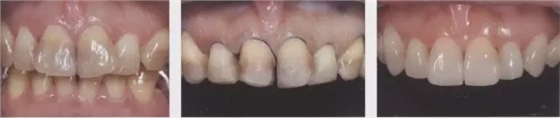

圖4牙頸部無變色病例。雖然變色很嚴(yán)重但由于未延伸到牙頸部(左圖),可進(jìn)行齦上成形(中),最終調(diào)整到了很自然的顏色。(右)